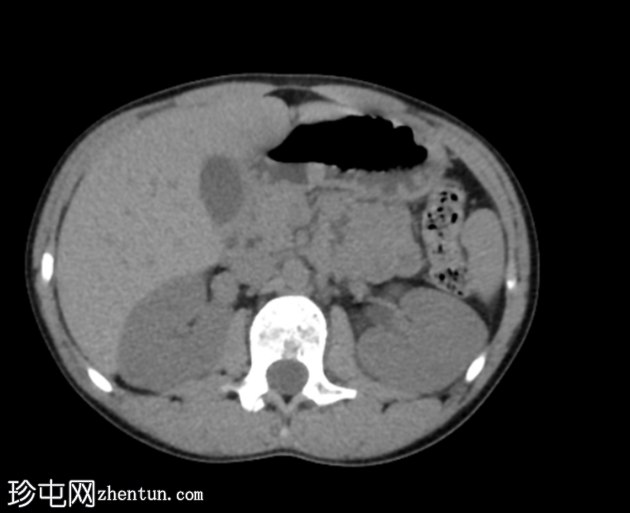

轴位

平扫

腹部和盆腔CT扫描结果正常。

泌尿系统正常。未见尿路结石或反流压改变。

本病例显示一名10岁男孩的腹部、盆腔和泌尿系统CT扫描结果正常。